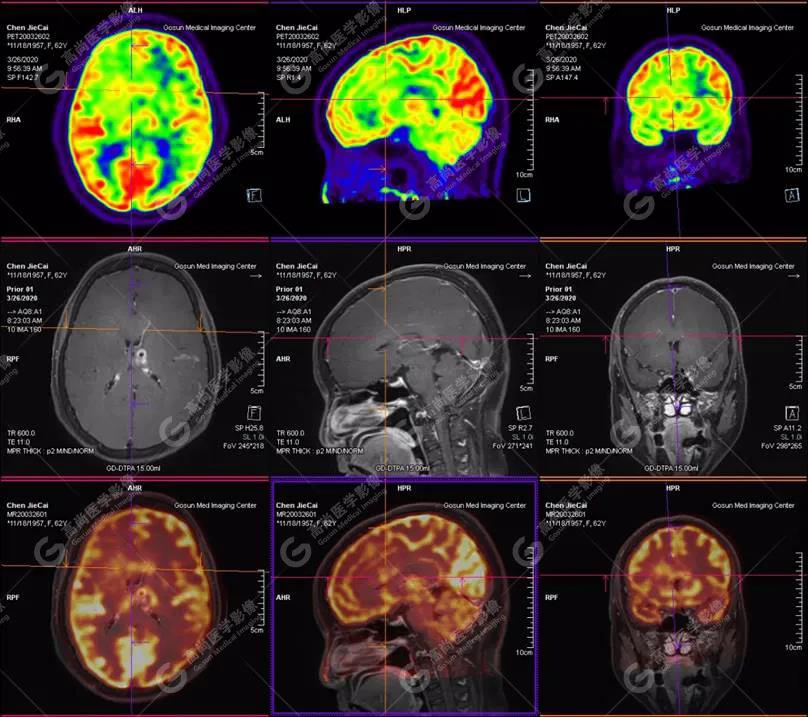

【廣東高尚醫(yī)學(xué)影像】多模態(tài)影像|顱內(nèi)淋巴瘤PET-MR融合顯像1例

影像圖

PET-MR融合診斷

左側(cè)顳葉、頂葉、左側(cè)基底節(jié)區(qū)及胼胝體部多發(fā)結(jié)節(jié)狀高代謝病灶,部分合并囊變、出血,MR平掃+增強(qiáng)示不均勻輕、中度強(qiáng)化,綜合考慮為顱內(nèi)原發(fā)惡性腫瘤,以淋巴瘤可能性大

淋巴瘤病變多位于中線兩旁的深部腦實(shí)質(zhì)、側(cè)腦室周圍及腦表面,甚少累及腦膜和顱骨,幕上多于幕下,呈分葉狀或握拳狀,水腫及占位效應(yīng)較輕,部分病灶內(nèi)可見囊變、出血及其邊緣的硬環(huán)征、尖角征、臍凹征,增強(qiáng)掃描呈現(xiàn)的“臍凹征或者“握拳征”是淋巴瘤較為特征性的一個(gè)表現(xiàn)。

PET/CT-MR檢查是原發(fā)顱內(nèi)惡性淋巴瘤的重要檢查方法,能有效提高診斷正確率;在早期發(fā)現(xiàn)、準(zhǔn)確分期、放化療后檢測(cè)具有極重要的作用。